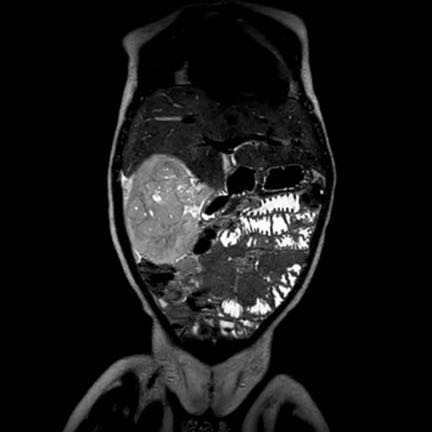

Ca lâm sàng 1

Hình ảnh chuỗi xung T2W mặt phẳng coronal cho thấy một khối u không đồng nhất ở thận trái với các thành phần nang nhỏ.

Khối u ngấm thuốc kém hơn so với phần nhu mô thận bình thường còn lại ở ngoại vi.

Các thành phần đặc của khối u cho thấy hạn chế khuếch tán rõ rệt (mũi tên).

Đây là u Wilms ở bé trai năm tuổi. Hóa trị tiền phẫu được thực hiện theo phác đồ Umbrella của SIOP-RTSG, sau đó tiến hành cắt thận.